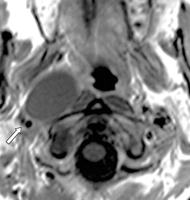

MRI scans help in better delineation of soft tissue masses. Its relationship with the carotids can be clearly seen in MRI.

MRI showing parapharyngeal mass